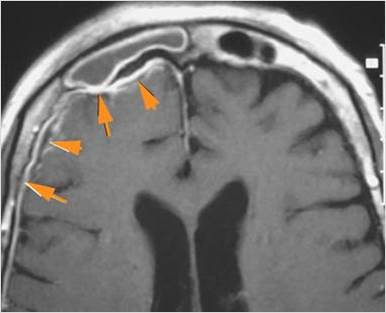

There is a subperiosteal fluid collection or abscess along the boney walls of the anterior or middle cranial fossa. [Yes/No]

There is an epidural fluid collection or abscess along the boney walls of the anterior or middle cranial fossa. [Yes/No]

There is a subdural fluid collection or abscess along the boney walls of the anterior or middle cranial fossa. [Yes/No]